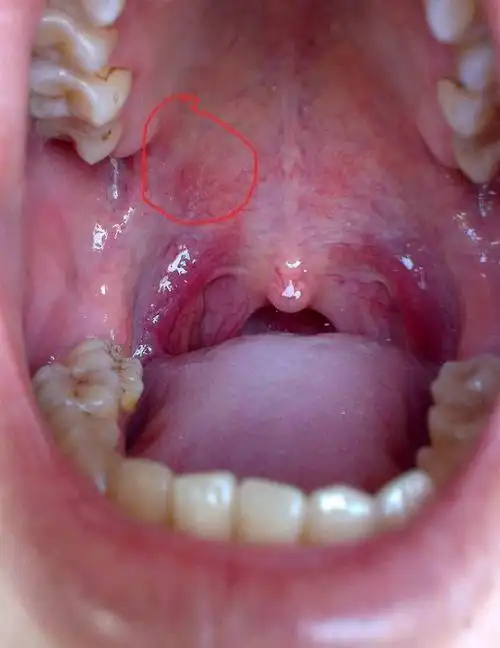

口腔上颚有红点

我的上颚不知怎么这样子了.突然发现的,没感觉疼痛

上颚长了一个疙瘩,不会痛,也不影响吃饭那些,请问这是口腔癌前病变吗?

上颚长个红色的疙瘩,请指导下这个是什么疾病呢?(急) [病例帖]

反复口腔斑片红肿疼痛一年多